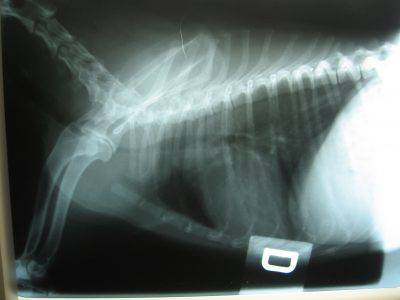

Estenosis cervical en perros

Es causada por la compresión de la médula espinal, generalmente al final del cuello. Aunque la compresión comienza desde el cuello, son las patas traseras las que se ven afectadas. La marcha puede pasar de inestable a temblorosa, mientras que en el caso grave se vuelve casi parálisis.

Las vértebras, debido a la presión del cuello, pueden deformarse y comprimirse. Esta compresión daña los nervios que transmiten información a las extremidades, provocando en consecuencia paresia (debilidad) o parálisis de las extremidades. Inicialmente, la presión afecta la capacidad del perro para moverse normalmente.

La inestabilidad vertebral apenas se siente al principio. La falta de coordinación puede tensar excesivamente los discos intervertebrales. Con el tiempo, si los discos se rompen, la médula se sobrecargará y se dañará irreversiblemente. Esto puede resultar en la aparición repentina de parálisis.